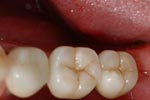

Caso finito